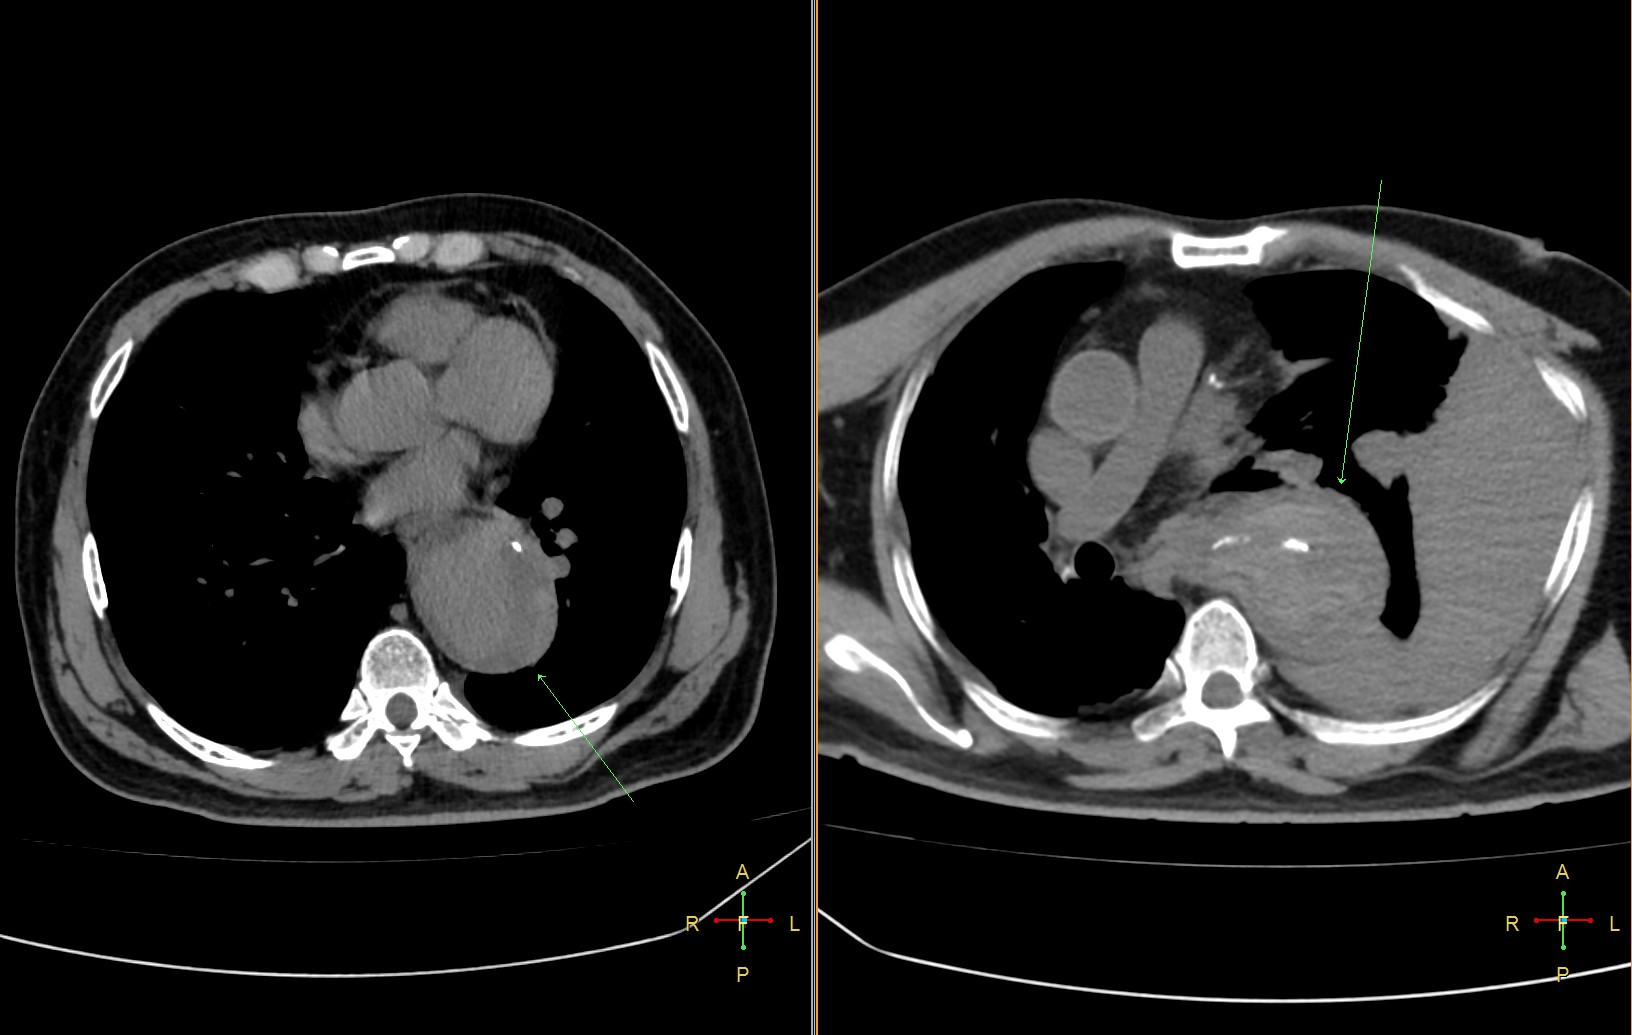

Ngày hôm sau, người đàn ông này bất ngờ hôn mê sau khi hắt hơi. Bác sĩ kiểm tra qua chụp CT xác định vỡ túi phình động mạch chủ khiến người bệnh shock và tử vong ngay sau đó.

- Phình động mạch chủ dọa vỡ: Đau tại vùng có túi phồng là dấu hiệu cảnh báo động mạch chủ sắp vỡ. Viêm quanh túi phình gây đau âm ỉ, có thể rò rỉ vào các tạng xung quanh (ống tiêu hóa, phổi). Đây là một cấp cứu ngoại khoa hoặc can thiệp. Các thăm dò chức năng cận lâm sàng như CT động mạch chủ ngực và siêu âm Doppler bụng có thể giúp chẩn đoán và điều trị.

- Bóc tách thành động mạch chủ: Là một biến chứng nặng nề, điều trị phức tạp, chẩn đoán xác định bằng chụp CT động mạch chủ.